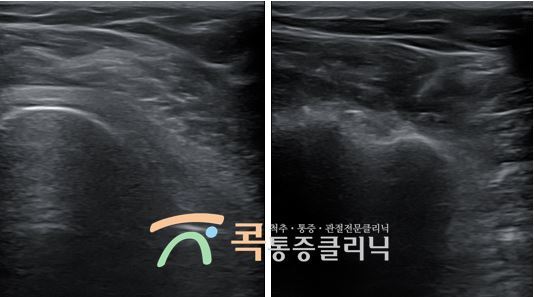

초음파유도하주사 치료(SI, sono guided injection)는 초음파 기기를 통증 부위에 대고 초음파를 인체에 투과시켜 진단과 동시에 주사치료가 가능한 방법인데요. 모니터를 통해 실시간으로 초음파 영상을 확인하며 환부에 약물을 직접 주입합니다. 디스크의 안정화 단계에서 특히 유용하며, 방사선을 쪼이지 않아 여러 부위를 치료해야 하는 환자에게 사용하기에 좋습니다.

CT나 MRI와 다르게 방사선을 사용하지 않고 인체에 무해한 초음파를 사용합니다. 고통 없이 정확하게 진단하며, 실시간으로 확인할 수 있다는 장점이 있습니다. 또한, 신경과 인대, 근육, 힘줄, 혈관, 관절 등 다양한 질환에 적용할 수 있습니다. 주삿바늘 자국 외에는 시술 흔적이 남지 않으며, 입원이나 전신 마취가 필요 없기 때문에 시간적 여유가 없으신 분들도 간편하게 받으실 수 있습니다.

콕통증클리닉에서는 MRI 대신 초음파를 활용해 정확한 진단 하에 초음파유도하주사 치료를 시행했습니다. MRI로 병변을 확인하지 않아도 초음파를 이용해 확인할 수 있는데요. 초음파를 이용한 주사 치료는 정확도를 99%까지 늘릴 수 있습니다.